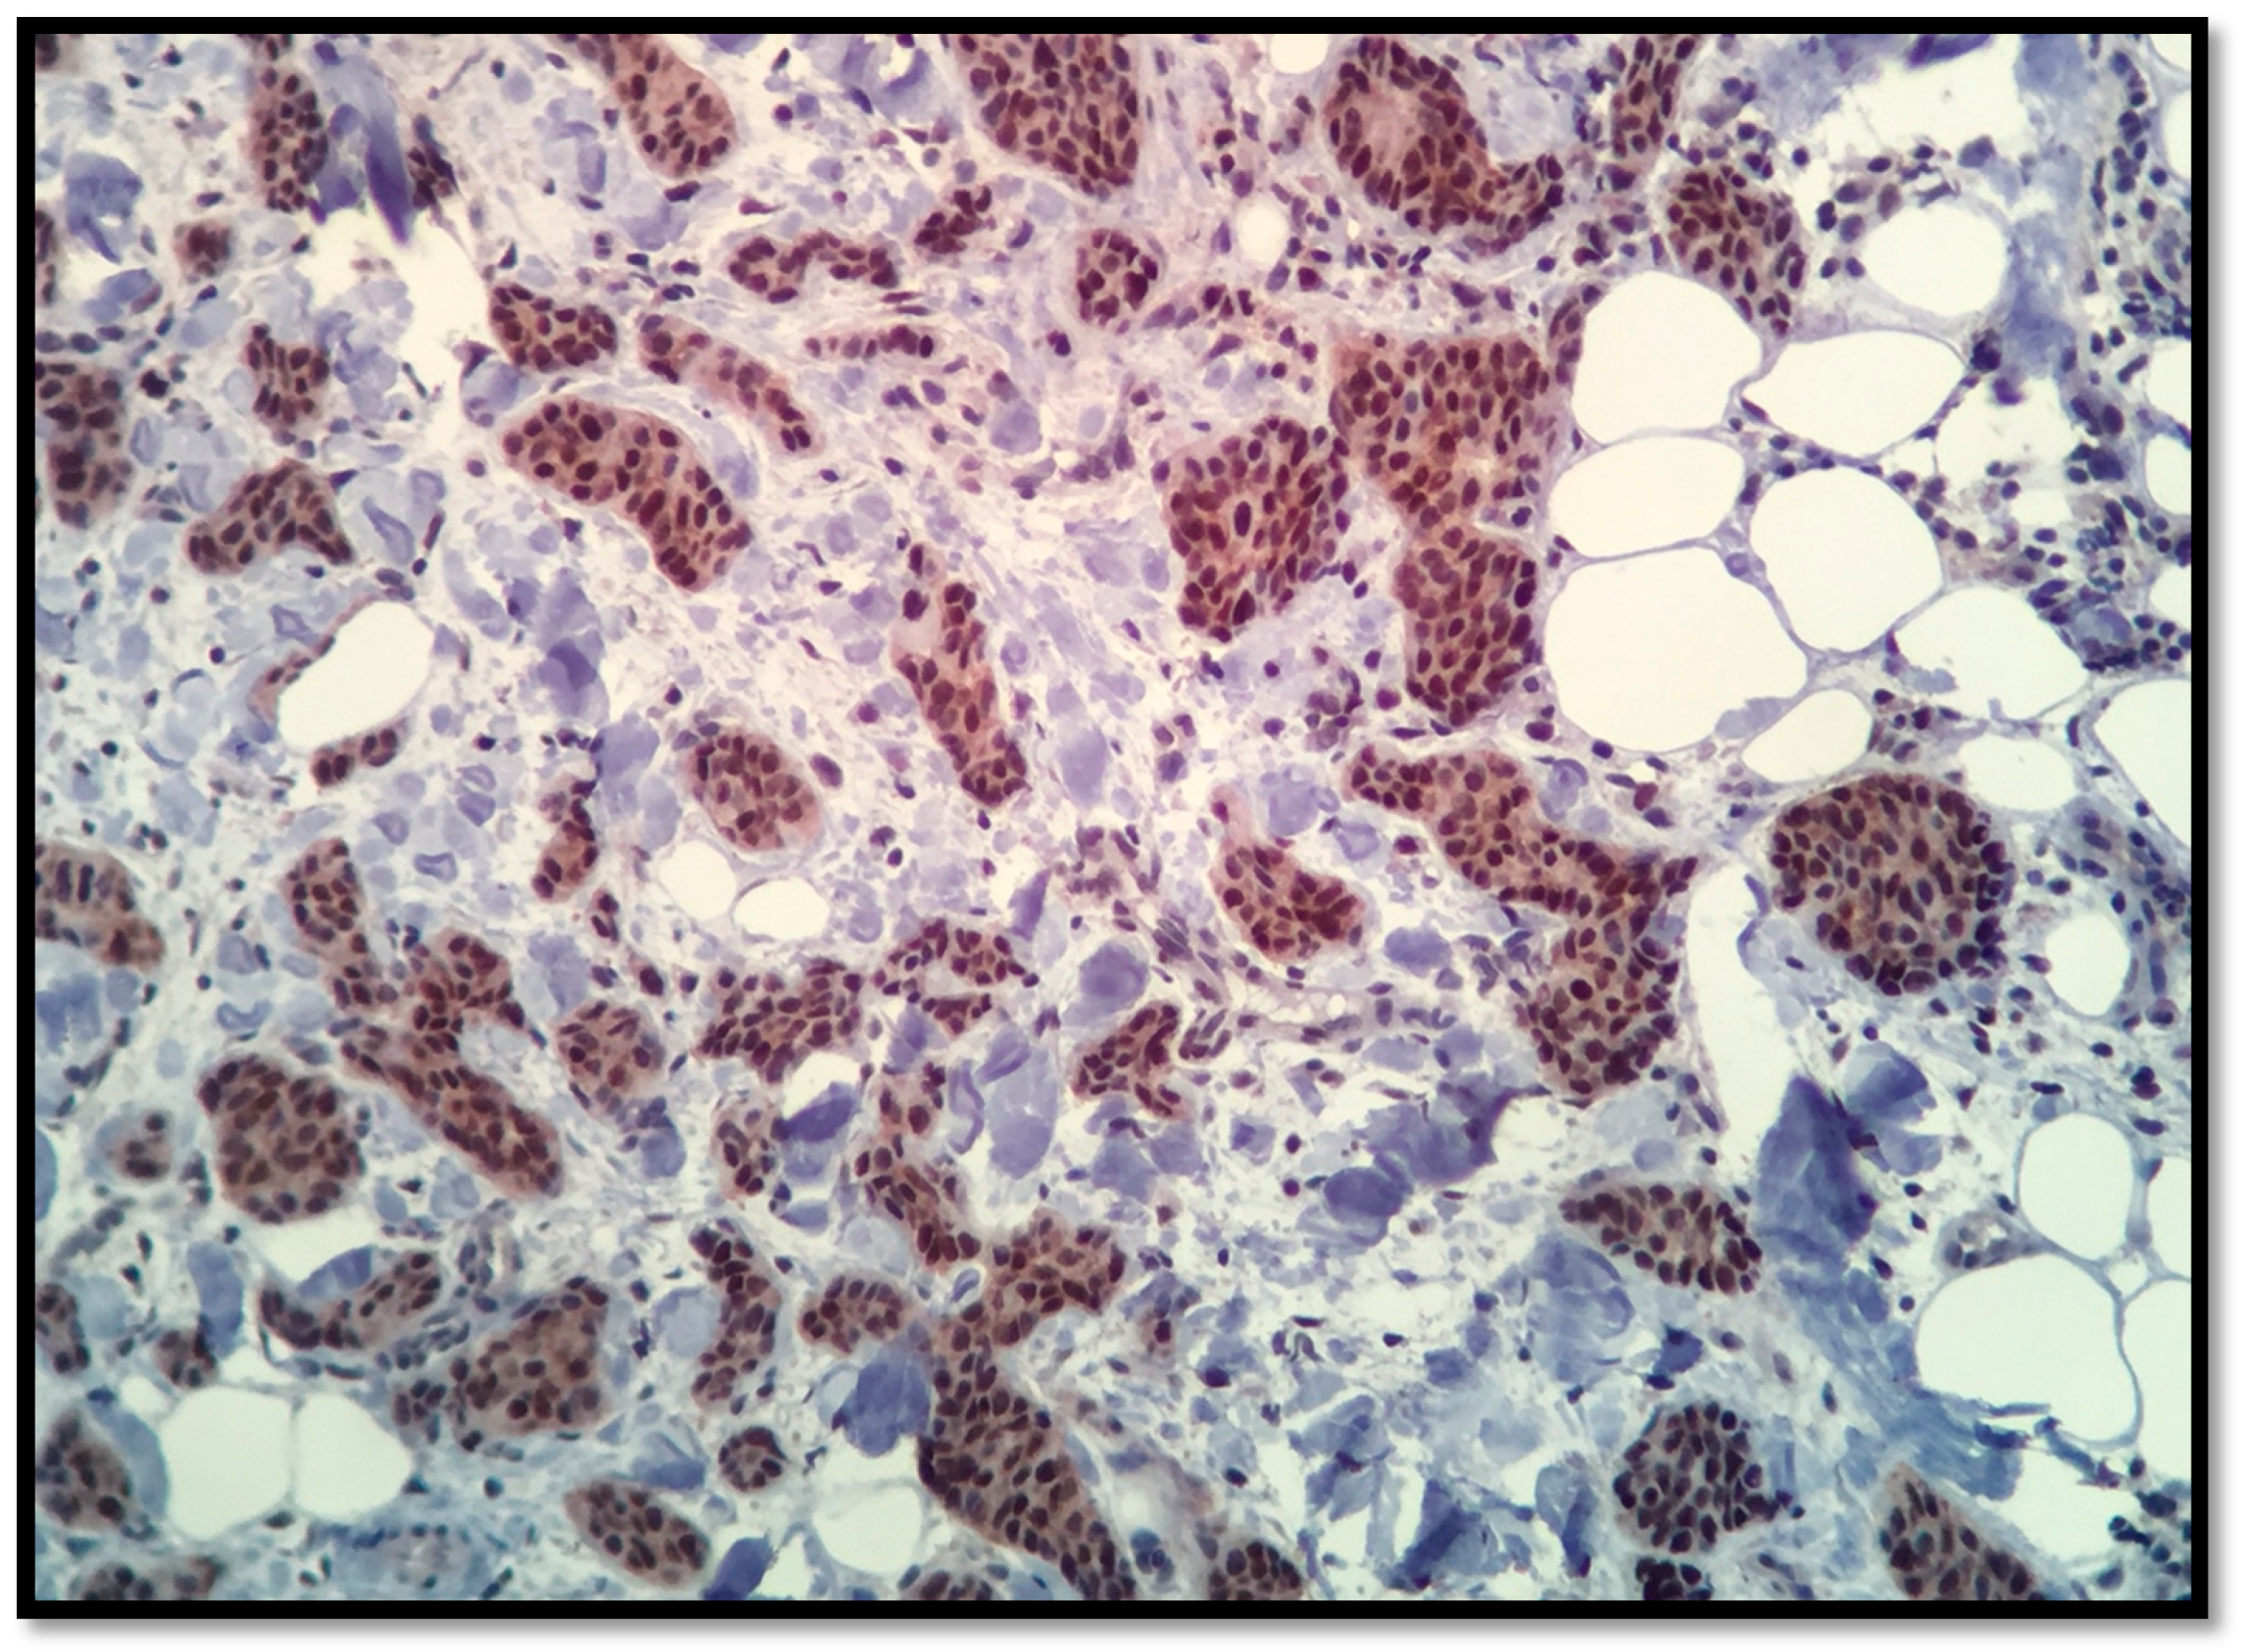

2.1. AR Assessment

3.1. Androgen Receptors

| IHC | AR ≥ 1% | Range |

|---|---|---|

| TNBC (n = 39) | 31 (80%) | 15–90 |

| R (−), Her 2/ neu (+), n = 22 | 14 (63% | 10–100 |

| R (+), Her 2/neu (−), n = 68 | 34 (50%) | 10–30 |

| R (+), Her 2/neu (+), n = 14 | 10 (71%) | 15–90 |